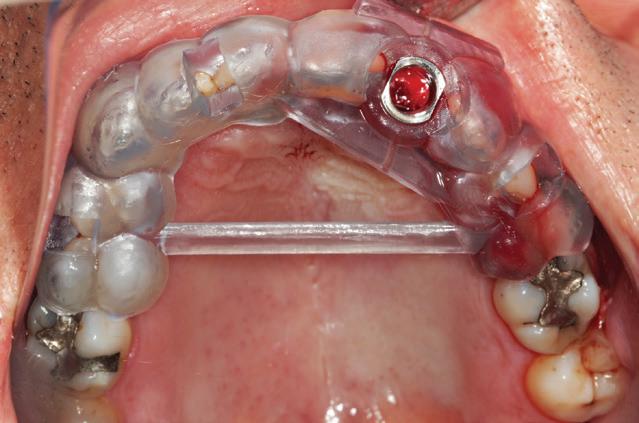

When I was working and studying in the U.K. in the very early 70s, I became interested and then became involved in implant dentistry. I was lucky to have mentors like Hans Orlay, Ron Cullen, Lou Caplan and others. One of my most vivid memories is of Leonard Linkow opening the First World Implant Congress in Paris in October 1972 with the words: “Behold the turtle, he only makes progress when he sticks his neck out”.

We already knew at that time that Titanium was biocompatible and that cells could grow towards it without needing an intermediary and this resulted in osseointegration. One of the practices where I worked was across the road from the Hawker Sidley aircraft factory which gave me access to pure Titanium. I obtained some pure Titanium, cylindrical wire which I planned to use if I ever decided to try doing some endodontic stabilisers as I figured that this would be better than the CoCr wire that Hans Orlay was using at the time.

I brought this back to Melbourne with me, together with my rather primitive implant kit, as well as a Kurer Post kit - no TGA rules in those days.

dry heat furnace, cut it to length less some 5 mm, coated it in endodontic sealer 10 mm short of the end to make sure that I didn’t extrude sealer past the apex, tapped it into place using my implant hammer and a Unitek pin placement tool and then using G.P. points, I sealed the tapering part of the root canal. I placed an amalgam seal on the lingual. The tooth became discoloured, the patient got married and moved to Queensland. I lost contact with him in the late 70s.

Fifteen years ago, I had to refer an elderly patient to an Oral Surgeon to have some teeth removed. We got a phone call at the surgery from her daughter who wanted to understand what was happening. I called back what was a Queensland number and identified myself to the man who answered the phone. On hearing my name, he identified himself and asked whether I remembered him. Of course I did. I asked him whatever happened to that tooth. He said that it didn’t cause any problems but that it had turned jet black and he and his wife got sick of looking at it. He’d had it extracted some 5 years earlier and it was replaced by a conventional implant. I asked him about the teeth either side of it and he said that they were still there and perfectly OK.

“The cliche that ‘when you are green you grow and when you are ripe you rot’ has never been more relevant. We have a public sector structure (and in this I include academia) that is mostly concerned with keeping itself employed and thus benefits from producing an ever-increasing regulatory burden without having to prove that this is to anyone’s benefit other than their own...”

In 1975, one of my patients who was 18 years old became involved in a car accident; he hit the steering wheel with his chin and sustained 2 horizontal fractures in his 31, both quite a way subgingivally. The 41 and 32 were intact. The normal treatment at that time would have required extraction of the 31 and the placement of a partial denture or a bridge to replace the missing tooth.

Knowing that he had nothing to lose, he agreed to let me experiment on him. I extirpated the 31, drilled 10mm past the apex using a sterile Kurer Post spiral drill that matched the diameter of my titanium wire. I sterilised the Titanium using a

Yes, I did stick my neck out, but the result ended being a lot better for the patient than if we had opted for a bridge or a partial denture. The biological cost was negligible and we bought him 30 years of function until a better and more modern treatment became available.

In the current regulatory environment, treatment such as I described is not only illegal and would result in crippling fines being imposed by the TGA, but possibly result in losing one’s right to practice. If I had made a conventional bridge, the teeth either side would have been compromised and possibly lost by now, a partial denture would have caused periodontal problems.

One case does not prove anything, but the result speaks for itself and sadly the option to use our knowledge and initiative is no longer open to us.